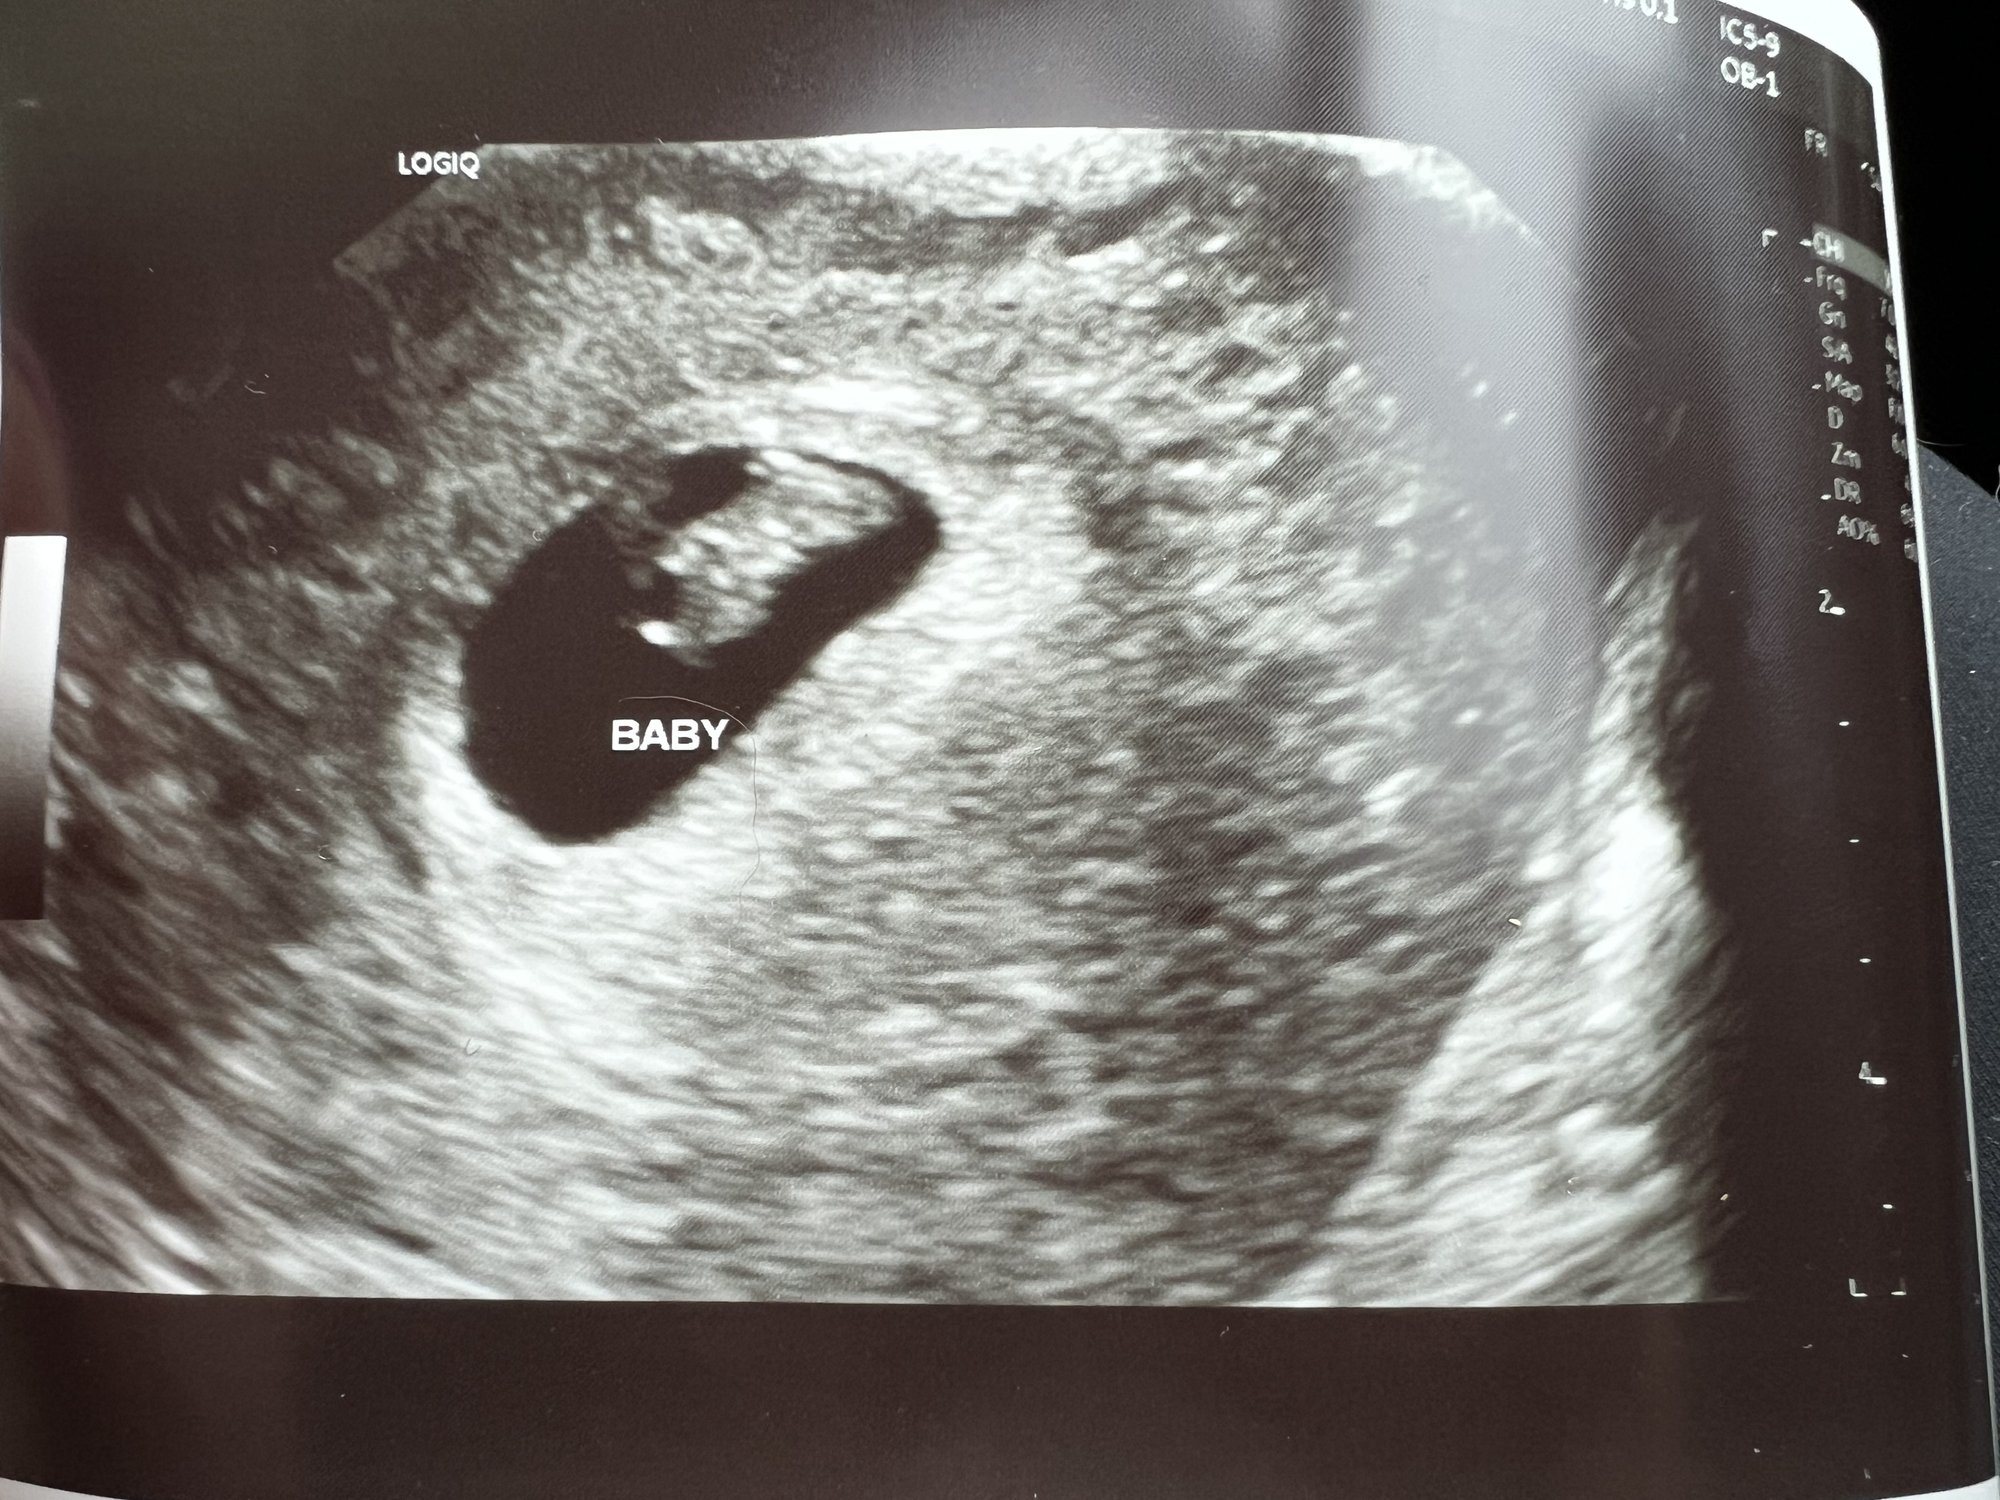

I have had three early miscarriages and at least two were blighted ovums so I was not expecting a positive test and DEFINITELY wasn’t expecting to see a heartbeat but here we are holding strong at 6 weeks 2 days!

Still early so with my history I’m not out of the woods but I have never seen a baby or heartbeat in my previous pregnancies, so I am very cautiously optimistic.